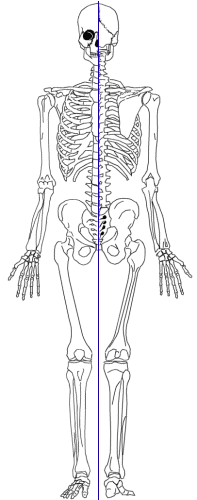

OSTEOLOGIE

On dénombre 24 vertèbres mobiles, dont :

Biomécanique

ses courbures selon la formule :

Les